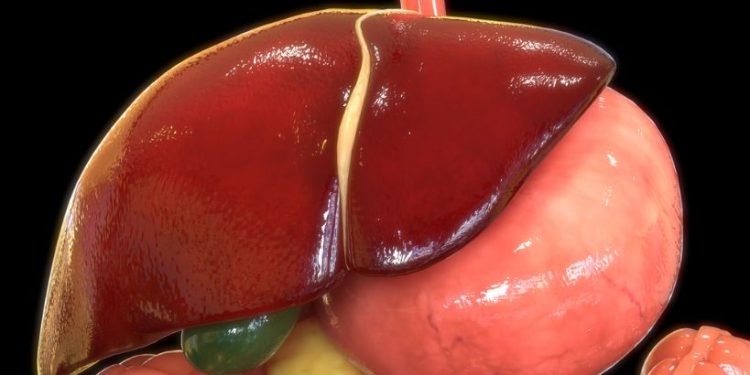

The most common type of liver cancer in adults is hepatocellular carcinoma, which starts in the main cells of the liver. Other types of primary liver cancer include intrahepatic bile duct cancer and angiosarcoma, which start in the cells that line blood vessels in the liver.

Primary liver cancer is more likely to occur in men ages 60 and older, but it can happen to anyone at any age. People who have cirrhosis, a condition that causes scarring of the liver tissue and increases the risk of developing liver cancer, are also at higher risk.